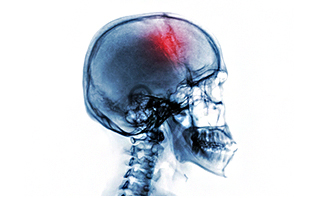

颅骨缺损是由外力导致颅骨缺损,从而引发的一些症状的疾病,颅骨缺损的症状挺多,有的患者会出现恐惧心理,对外界事物的排斥,其影响很大,要及早治疗才是对患者健康的负责。那么颅骨缺损的症状有哪些呢?

1、颅骨缺损处局部表现

局部有胀痛,缺损边缘疼痛,不能忍受的脑搏动,缺损部高位时头皮向颅内陷入;缺损部低位时,头皮甚至合并部分脑组织、脑室向外膨出。

主要表现为头痛、头昏,患者对缺损区的搏动、膨隆、塌陷存恐惧心理,怕晒太阳、怕震动甚至怕吵闹声,往往有自制力差、注意力不易集中和记忆力下降;或有忧郁、疲倦、寡言及自卑。

3、长期颅骨缺损

有脑膨出或突出时,脑组织可萎缩及囊变。小儿颅骨缺损随脑组织发育而变大,影响正常脑发育而出现智力偏低;成年人可出现反应迟钝、记忆力下降甚至局灶性神经系统症状、体征。脑膜-脑瘢痕形成时可伴癫痫。